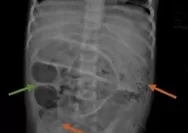

Saat dody menUSG terlihat di monitor ginjal kirinya ada batu tiga biji yang sudah turun dengan ukuran 0,5 senti, inilah penyebab keluhan rasa sakit yang diderita pasien.